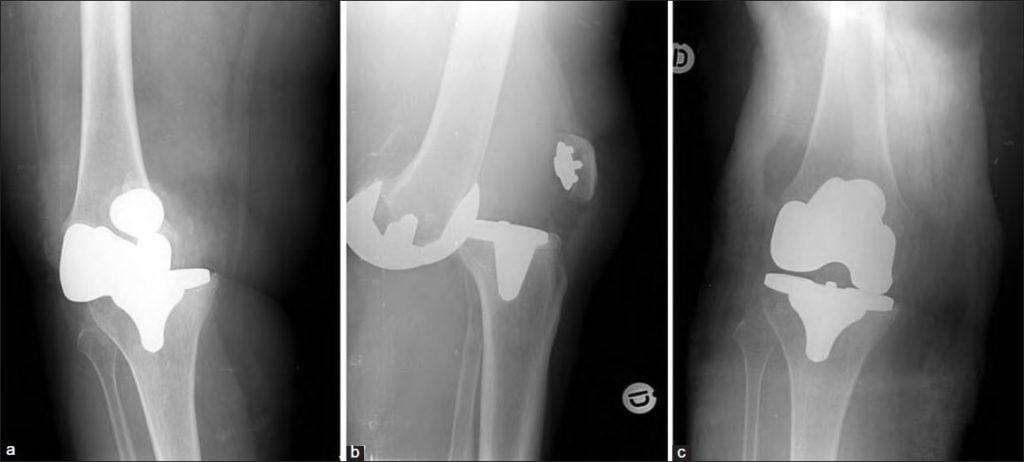

Реабилитация после эндопротезирования имеет первостепенное значение для обеспечения безболезненного функционирования сустава и улучшения качества жизни пациента. Операция по замене коленного сустава показана для лечения болезненных и инвалидизирующих патологий, вызванных различными формами артрита, тяжелыми травмами. Хирургом-ортопедом выполняется полная или частичная замена износившегося суставного соединения на его анатомически точную копию.

Искусственный имплантат состоит из металлических и пластиковых элементов, абсолютно безопасных для организма. Чтобы заново научить прооперированную конечность двигаться правильно, расширить диапазон доступных движений, требуются массажи, посещение физиотерапевтического кабинета, выполнение комплекса упражнений.